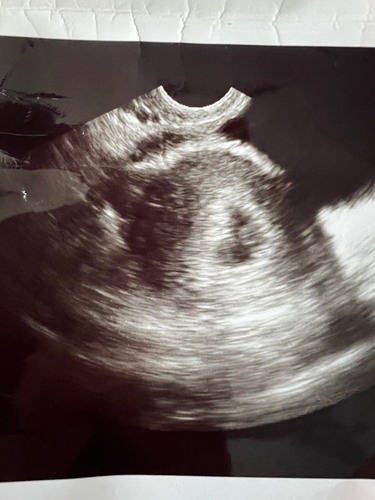

Mijn echo gisteren, uitwendig. Heeft iemand een idee wat het witte stipje bij baby B is? Bij baby A zag ik dit niet. Het viel mij net pas op. Dit is trouwens een uitwendige echo. Baby B is 7w2d op deze echo. En baby a 7w3d. Vandaag weer een dagje verder natuurlijk:)

En baby a beter in zicht.